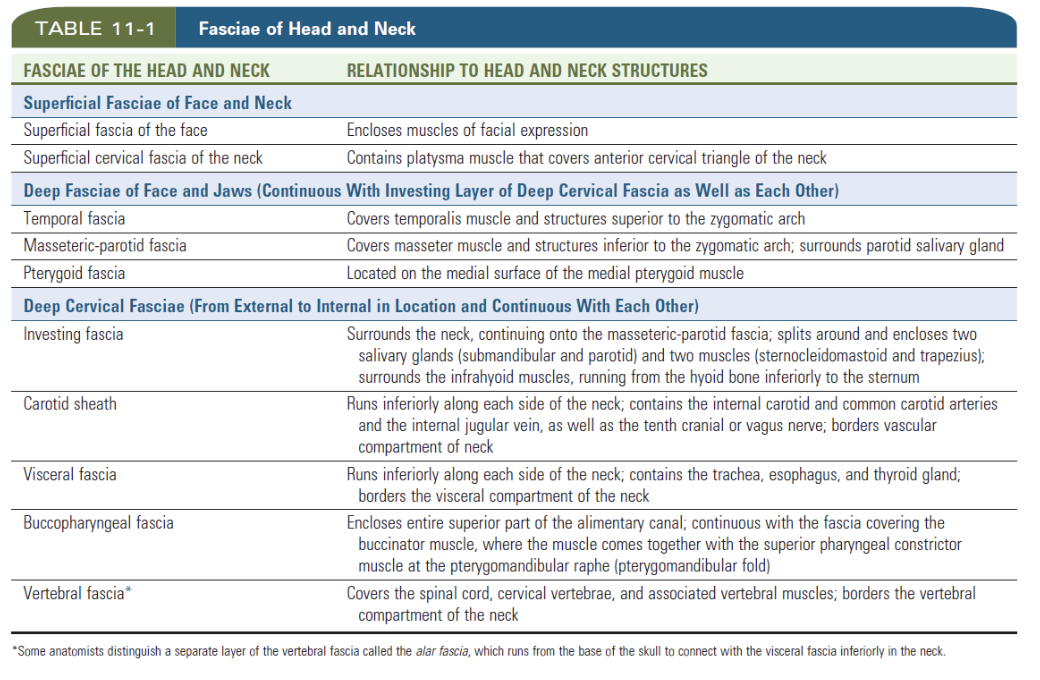

Fasciae

Superficial fascia

- 表情肌

- Platysma

Deep fascia

Head

- Temporal fascia

- Temporal arch以上

- Masseteric-parotid fascia

- Temporal arch以上

- 連到investing fascia

- Buccopharyngeal fascial

- 連到investing fascia

- Pterygoid fascia

- Pterygoid m. 外

Neck

-

Investing fascia

- 最外層

-

Carotid fascia

-

Visceral fascia

- 食道呼吸道

-

Vertebral facial